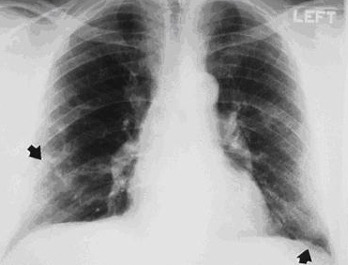

Posterior-anterior view of the chest with 'mesa'-like pleural thickening of the left diaphragm and 'in-profile' pleural thickening of the mid zones of both the left and right lungs

From the personal collection of Kenneth D. Rosenman MD